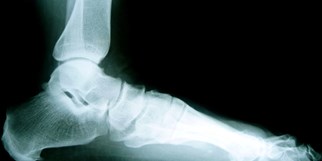

Beim Sichelfuss (Pes adductus)

hat der Fuss die Form einer Sichel, indem der Mittelfuss und die Zehen

zu stark nach innen abweichen. Der Sichelfuss kann